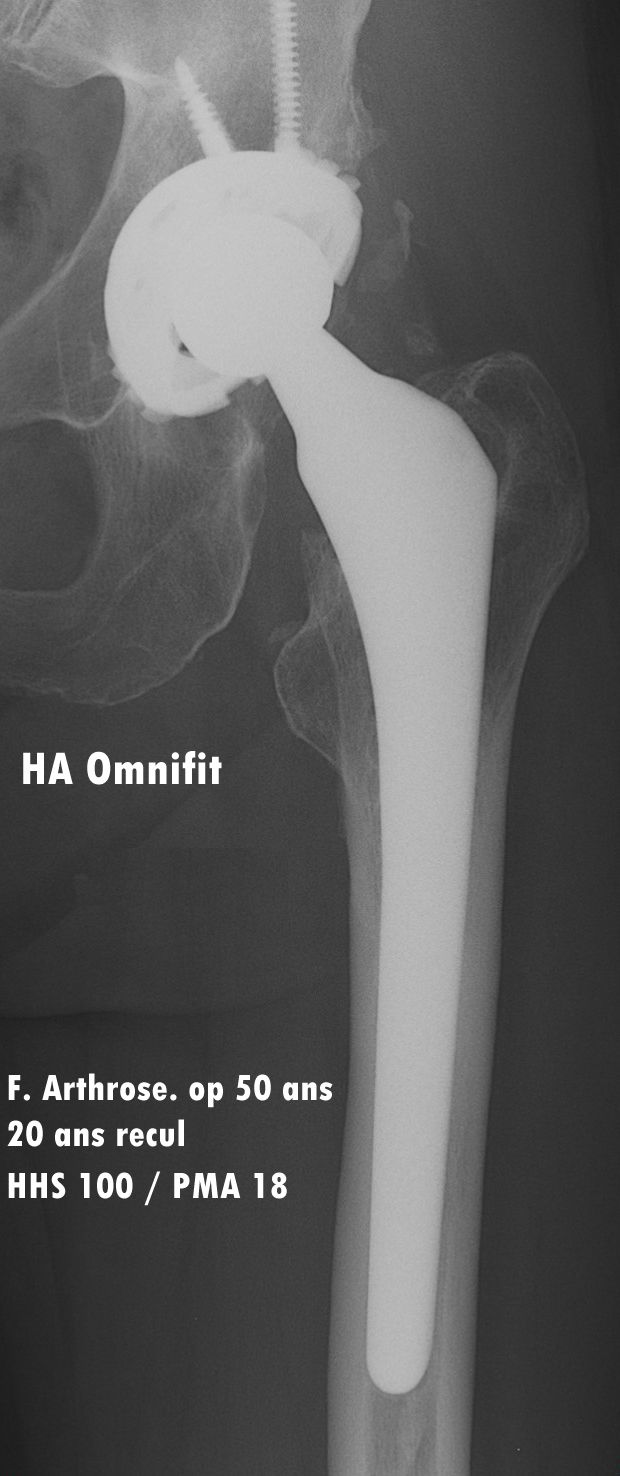

The minimum follow-up for the study was 20 years, and it encompasses two families of proximally HA-coated stems, first the Omnifit HA, which was used between 1987 and 2000, followed by the ABG II from 2001 onwards. Both models are made from titanium alloy coated with a thin layer of hydroxyapatite (60 microns) on their proximal third to provide a ‘metaphyseal-engaging’ design. As counterpart to the stem, the acetabular component used until 2007 was the Arc 2F HA-coated screwed cup comprising a standard PE insert until 1998 then a ceramic-on-ceramic cup in 1999 and 2000, replaced with a highly crosslinked PE insert in 2001.

The Harris Hip Scores (HHS) [28] for this series were 40.07/100 (21–67; SD 10.35) at baseline vs. 99.39/100 (86–100; SD 2.5) at 10 years, then 99.83 (97–100; SD 0.71) at 20 years and finally 99.44/100 at last follow-up (88–100; SD 3.02). Over the years there was therefore no deterioration in clinical outcomes, with an overall average HHS score of over 99 points for all cohorts. Likewise for PMA, with a total score of 8.15/18 (3–16; SD 2.02) at baseline and 17.75/18 (11–18; SD 0.89) at last follow-up, with an 89.5% rate according to the Forgotten Joint Score.

Overall, these proximally HA-coated stems demonstrated excellent osteoapposition, optimal radiological fixation with bone growth in all cases, and no deterioration in outcomes even after 20 years. (Figs. 3, 4 & 5).